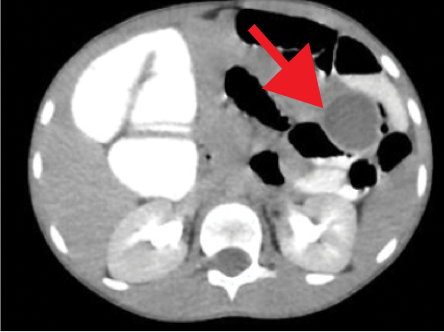

The contrast-enhanced computed tomography (CECT) abdomen findings were as follows: The D3 segment of the duodenum was seen to cross to the left side with the duodeno-jejunal junction in its expected location. The superior mesenteric arter-superior mesenteric vein (SMA-SMV) relationship was maintained with the SMV lying on the right side of SMA. The small bowel loops were predominantly on the left side of the abdomen, and the entire colonic loops were positioned on the right side of the abdomen [Figure 1]. The ileocecal junction (ICJ), cecum, and appendix were noted in the right lumbar region [Figure 2]. The inferior mesenteric artery was seen coursing to the right side of the midline, rather than its normal left-sided course [Figure 3]. A tubular cystic lesion was observed in relation to the small bowel loops on the left side of the abdomen [Figure 4]. Intrabdominal solid organs were essentially normal, with a normal situs.

Figure 4: Axial sections of contrast-enhanced computed tomography abdomen showing a well-defined fluid filled cyst (red arrow) on the left side of the abdomen in relation to the small bowel loops.